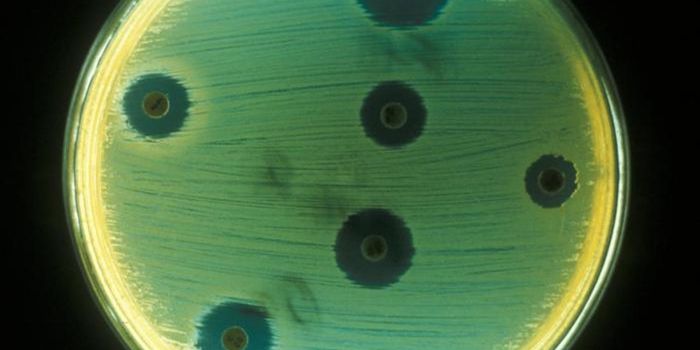

APR 03, 2018MicrobiologyAntibiotic resistance is a major public health concern. Around 23,000 Americans die of an antibiotic-resistant infection ...

NOV 25, 2019Drug Discovery & DevelopmentEvery year, around 700,000 people are estimated to die from drug-resistant infections thanks to our overuse of antibioti ...

APR 09, 2015MicrobiologyResearchers from the University of Exeter, UK, have shown that the use of ‘sequential treatments' - using alternating do ...